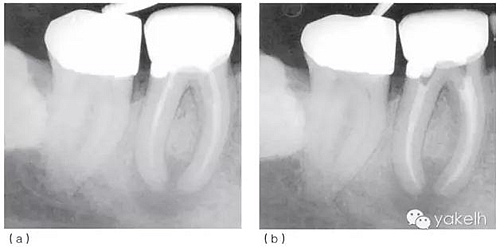

局麻下放置橡皮障隔離術(shù)區(qū),拆除現(xiàn)有修復(fù)體,去除樁周圍的核,使用超聲器械使樁松動并拔出。臨床檢查可見46遠中邊緣位于齦下2mm,DOM下觀察發(fā)現(xiàn)剩余牙體結(jié)構(gòu)完好且可修復(fù)。46臨時用不銹鋼帶環(huán)加固和玻璃離子水門汀充填(圖5.1.2a)。放置帶環(huán)的目的是容納充填材料并保護患牙的完整性。

2周后復(fù)診,患牙隔離和消毒同前;保持干燥(使用低速球鉆,避免污水再次進入患牙),去除暫封材料;次氯酸鈉和EDTA沖洗進行根管再預(yù)備;紙尖干燥根管;使用牙膠和根管封閉劑充填根管;在遠中根管內(nèi)預(yù)備樁道;窩洞用復(fù)合樹脂充填(圖5.1.2b)。

圖5.1.2(a)46根管再治療前X線片。現(xiàn)有修復(fù)體、核及兩個不銹鋼樁均已安全拆除,患牙用不銹鋼帶環(huán)和Ketac-SilverTM臨時修復(fù),這為后續(xù)治療提供了無微滲漏且穩(wěn)定的局部環(huán)境。(b)46根管再治療后X線片。與圖5.1.1相比,根管預(yù)備和充填更接近理想的工作長度,致密度更高。